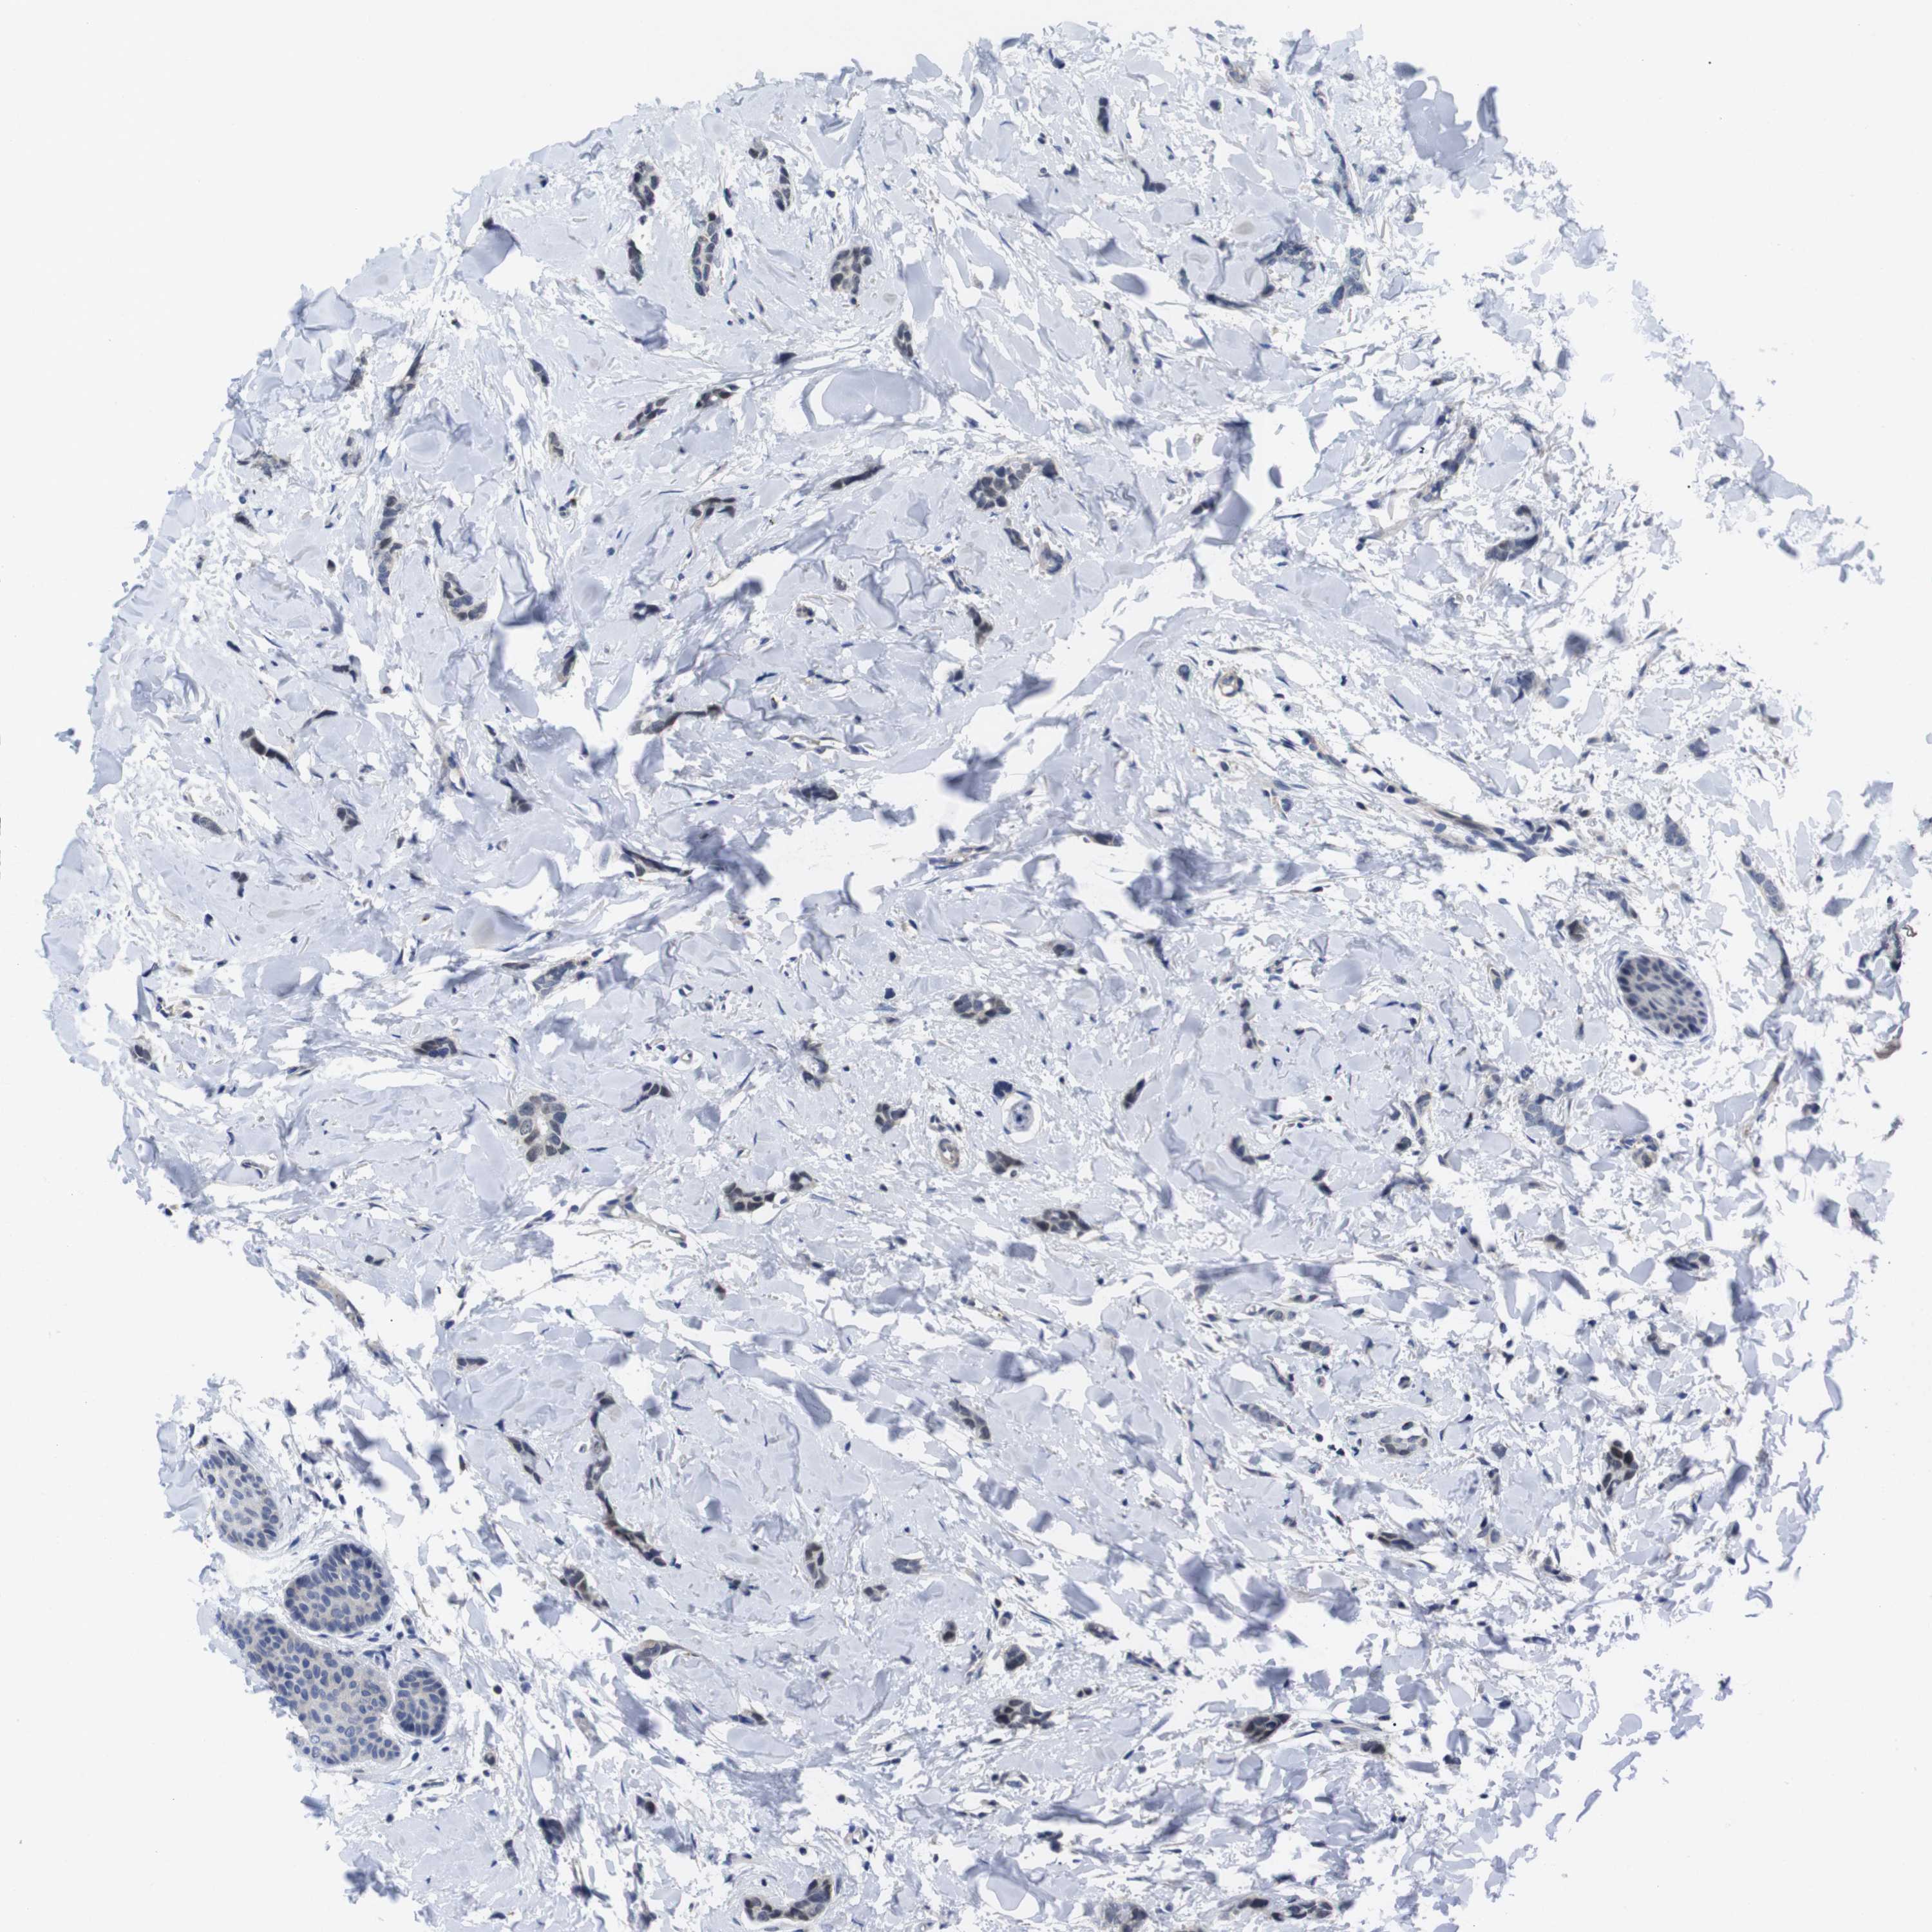

CANCER BREAST CANCER Show tissue menu

BRCA TCGA BRCA VALIDATION PROTEIN EXPRESSION

ANTIBODIES